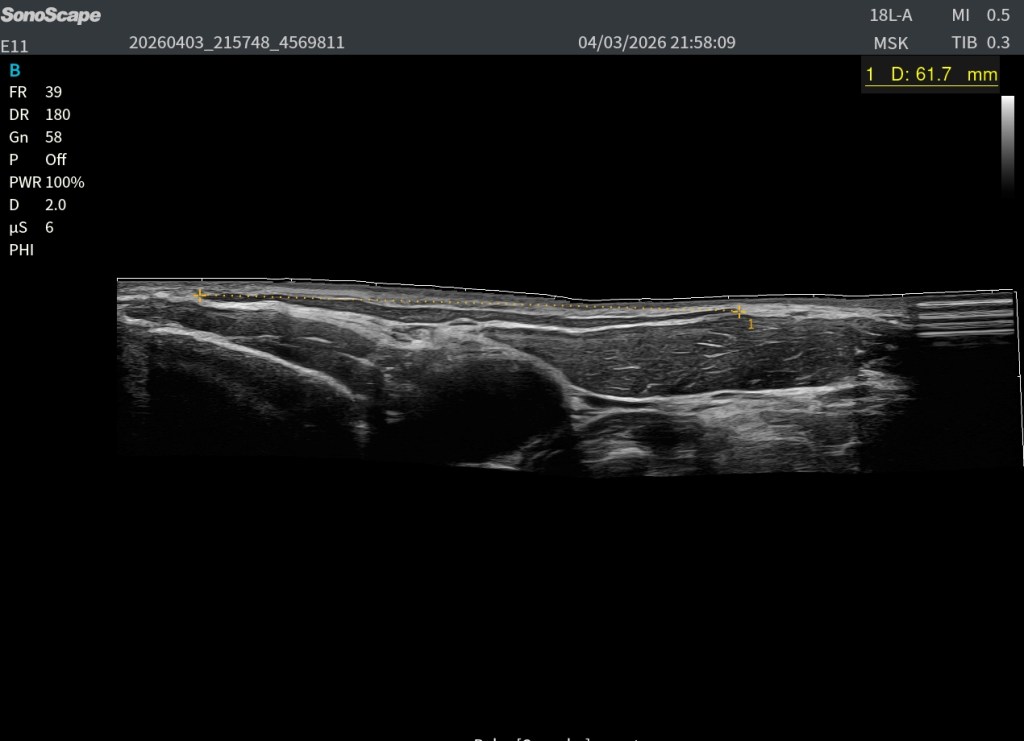

El Platisma se presta especialmente bien a la evaluación mediante técnicas de campo extendido. Utilizando el modo panoramic view, es posible realizar un recorrido continuo del músculo y obtener una visión global de su extensión, algo muy útil dada su morfología plana y superficial.

La exploración puede realizarse en eje axial (corte corto respecto al cuello), desplazando la sonda de forma progresiva a lo largo del trayecto del músculo. Esto permite visualizar su continuidad lateral y entender mejor su disposición en el plano subcutáneo. También puede intentarse un estudio bilateral, tratando de integrar ambos lados en una única imagen panorámica.

Sin embargo, esta técnica presenta cierta dificultad al atravesar la región central del cuello, especialmente sobre la tráquea, donde la superficie es más irregular y la transmisión del movimiento de la sonda es menos homogénea. Esto puede generar artefactos o discontinuidades en la reconstrucción de la imagen.

A pesar de estas limitaciones, el platisma, por ser un músculo muy extenso, plano y superficial, se adapta bien a este tipo de exploración, y la panoramic view se convierte en una herramienta especialmente útil para comprender su anatomía global y su continuidad. Podemos medirlo tambien.